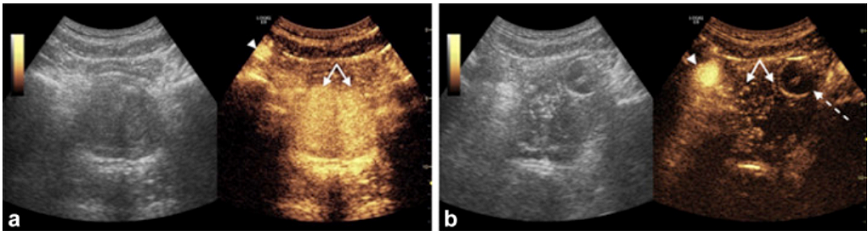

15 prostatic arteries, when injected with contrast, enhanced that half of the prostate as demonstrated by IA CEUS. All 15 again demonstrated decreased enhancement after embolization of the arteries. IV CEUS is used for 4 patients, and this also demonstrated decreased enhancement for 100% of the arteries after the embolization. All patients reported improvement in symptoms in 6-week follow-up, implying that the procedures are likely all successful.